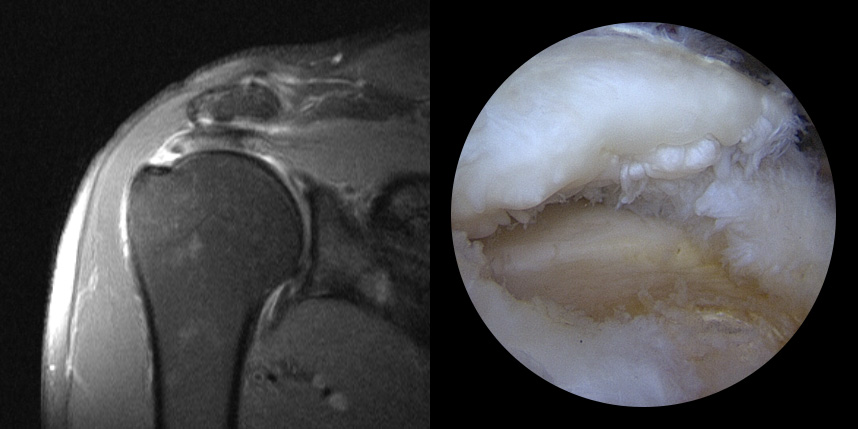

어깨 안에는 어깨 관절을 감싸고 있는 4개의 힘줄이 있습니다.

이 힘줄이 회전근개이며, 회전근개는 관절이 가능한 움직임 내에서 안정성을 유지하는 역할을 하고 있습니다.

이런 회전근개가 하나 또는 그 이상 파열되는 것을 회전근개 파열이라고 합니다.

회전근개파열은 파열정도에 따라서 치료법이 달라집니다.

완전 파열시

브릿지 봉합술